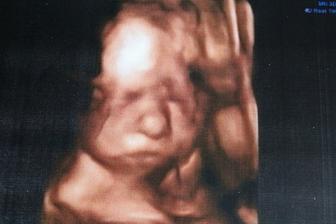

3.6. 4D ultrazvuk v Heliosu, moc mila pani doktorka, ale kozena nase mela celou dobu nacpane nozky pred ksichtikem, dumlala si palecky u noh, popripade si tam nacpala jeste i rucicky. Nepomohly drepy, poskakovani - nic. Mame cca 20 min video, kde jsou ovsem videt jen zablesky obliceje, ale i tak to stalo za to 😉 Holcicka potvrzena i tady, vazi pres 800 g.